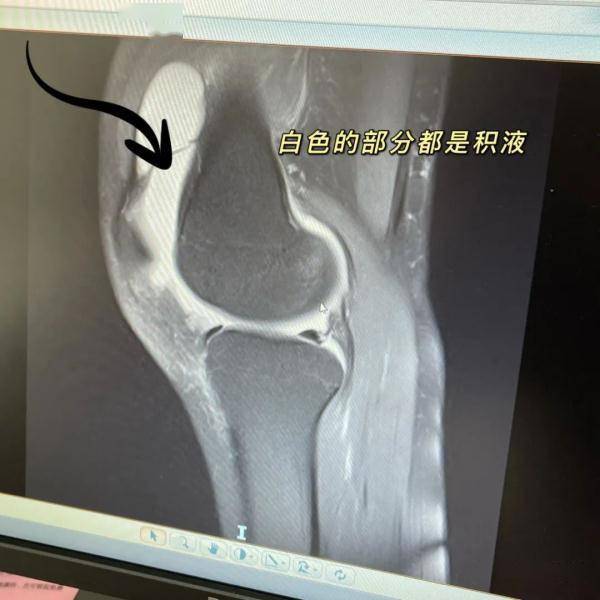

就诊时馒头大的膝盖里都是积液

孙主任说 , 在排除了外伤的前提下 , 他判断女生是由于滑膜炎而引发的积液 , “因为来医院之前她的膝盖已经痛了十来天 , 而且这期间还在上班 , 膝盖没有得到休息 , 也没有做好保暖 。 ”

做过检查后 , 果然膝盖里的空隙处都是液体 。 “我当时给她把积液抽出来 , 针筒扎进去 , 都不用抽 , 关节里的压力就压着积液直接流了出来 。 我叮嘱她回去戴一段时间的半月板护膝 , 然后多休息 , 减少走路 , 避免爬山、爬楼梯 , 注意保暖 , 之后也要适当进行运动 。 ”